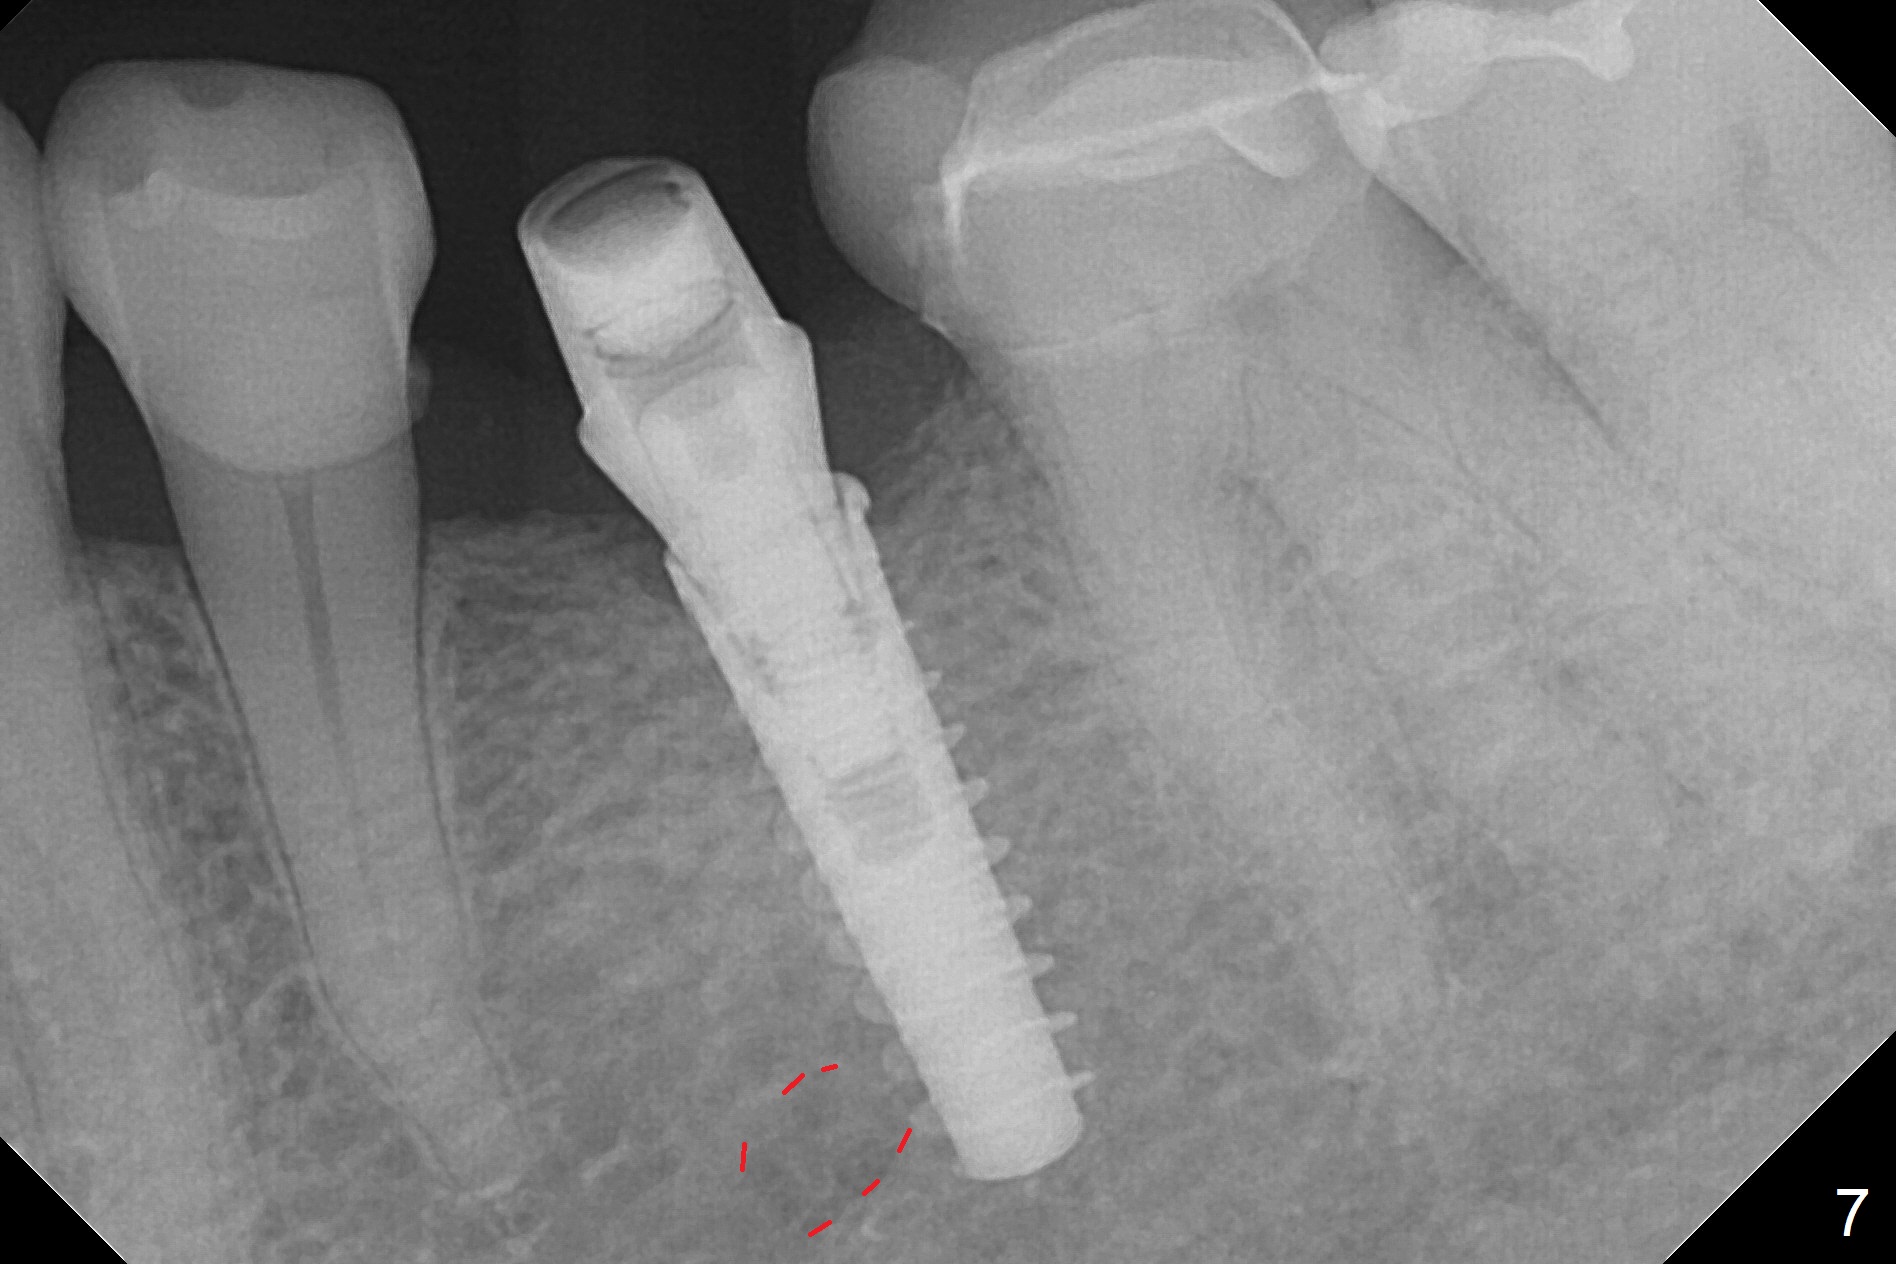

Initial osteotomy with 1.6 mm drill for 11 mm seems to be distal (Fig.1). The trajectory should be changed as shown by the black line in Fig.2; the drawback would be close to the Mental Loop (red line). Fortunately the trajectory is changed, but not so much as to be close the Loop when a 4x11 mm dummy implant is placed (Fig.3). When a 4x13 mm IBS is placed with 46 Ncm, there is clearance from the Loop (Fig.4-6). In fact there is no postop paresthesia. The main point is no block anesthesia. Infiltration anesthesia is administered with 34 mg Xylocaine with 17 mcg Epinephrine. The patient experiences dull pain when the implant is placed (Fig.4-6). After further anesthesia with 68 mg Septocaine, 17 mcg Epinephrine, the implant is torqued for a few turns (still with some discomfort). Finally autogenous bone with Osteogen is placed around the implant following placement of a 4.5x4(2) mm abutment. To reduce anxiety, a shorter implant should have been used. The patient complains of cold sensitivity in the lower left quadrant 4 months postop (Fig.7): the implant apparently close to the Mental Loop. Without an immediate provisional, the gingiva around the abutment is healthy.